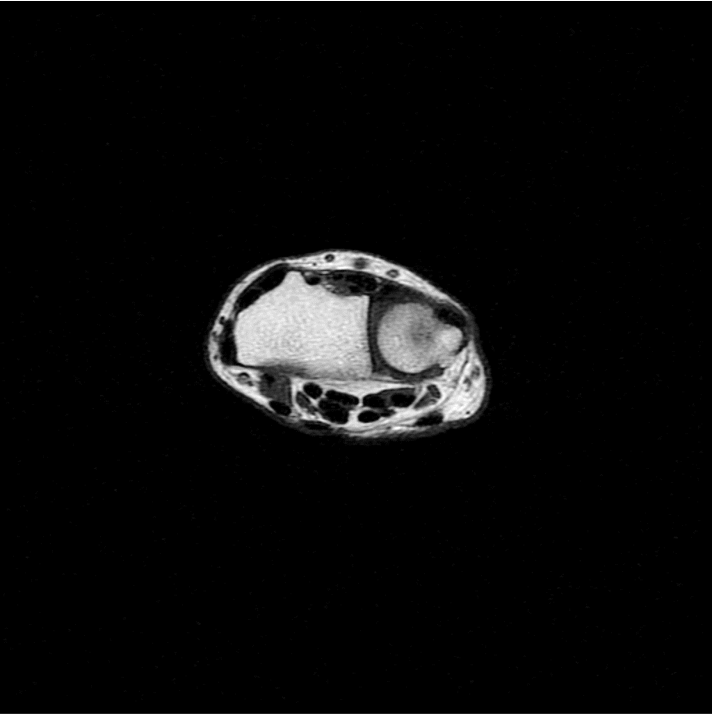

standard

384 x 256 (4 NEX)

3:02 minIAI (Innovative AI)

384 x 256 (2 NEX)

1:30 minReduced Scan Time